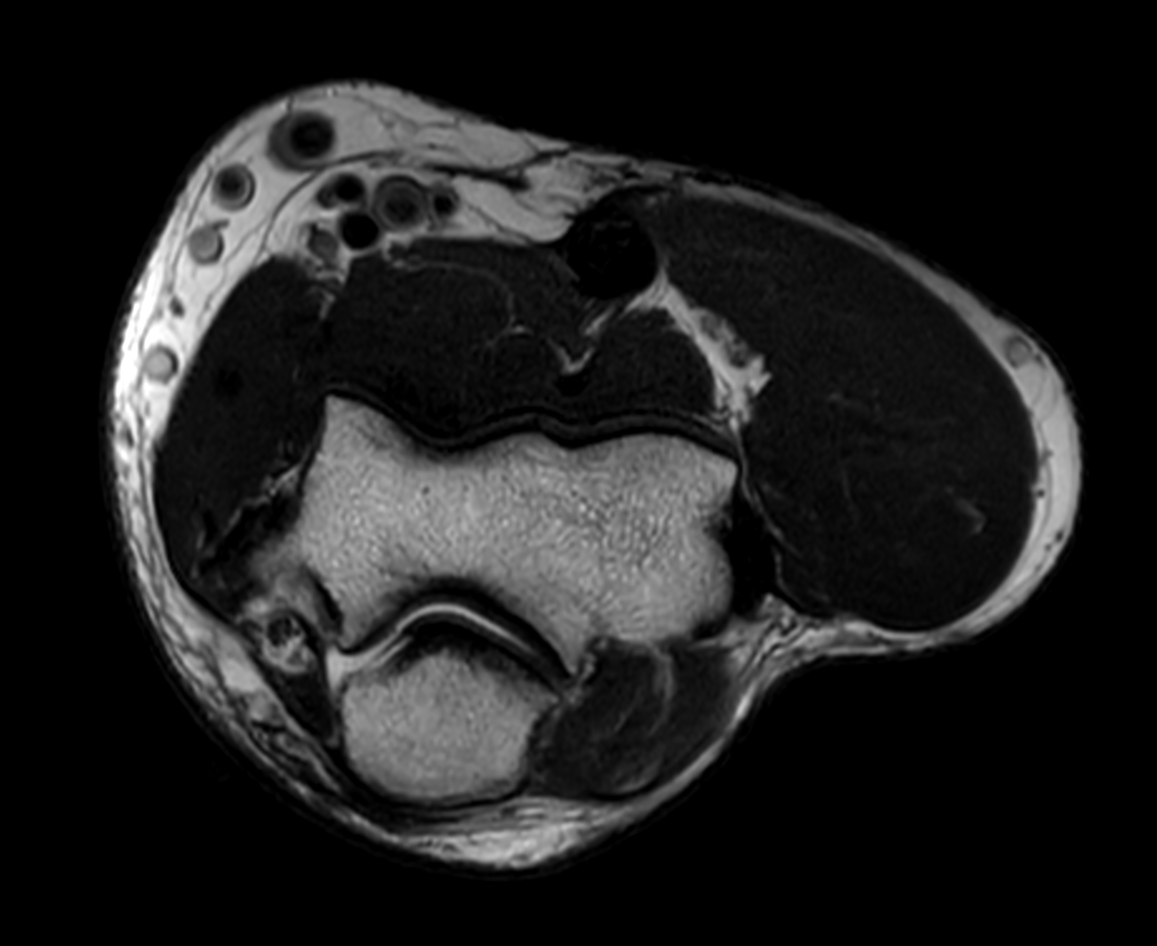

Axial PDw mDIXON XD TSE (Water only)